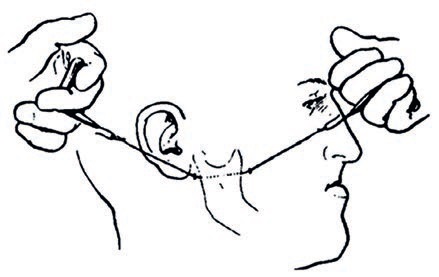

Łączne leczenie ortodontyczne i chirurgiczne ciężkiej wady zgryzu klasy III ze zgryzem krzyżowym przednim i tylnym

W niniejszej pracy kazuistycznej przedstawiono przypadek dorosłego pacjenta z ciężką szkieletową wadą zgryzu klasy III, z ewidentnym niedorozwojem szczęki i nadmiernie rozwiniętą żuchwą, co powodowało zgryz krzyżowy przedni i tylny, a także przesu...

60 lat innowacji w biomechanicznej chirurgii ortognatycznej: stan wiedzy i kierunki na przyszłość